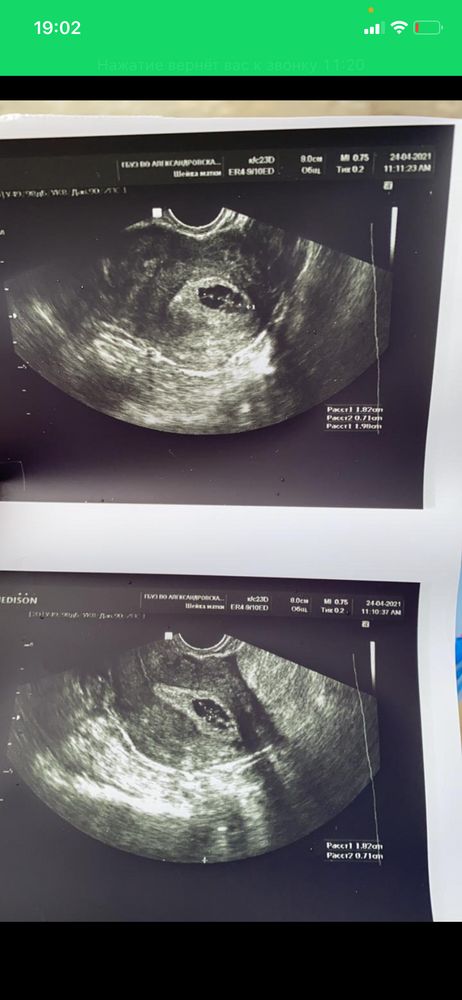

Скажите как гематома выходит??? И каак она выглядит на узи?

у подруги нашла Типо как Два ПЯ..один на верху, и другой в самом низу уже..может это гематома была? Кровило очень сильно

Diana rog, вот снимок гематомы . У меня 2 дня кровило , снимок сделан после того , как все прекратилось . Читала , что она потом рассасывается